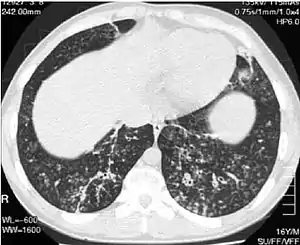

High-resolution computed tomography scan of the thorax

High resolution computed tomography (HRCT) images of the lower chest in a 16-year-old boy initially diagnosed with DPB (left), and 8 weeks later (right) after a 6-week course of treatment with erythromycin. The bilateral bronchiectasis and prominent centri-lobular nodules with a "tree-in-bud" pattern shows noticeable improvement.